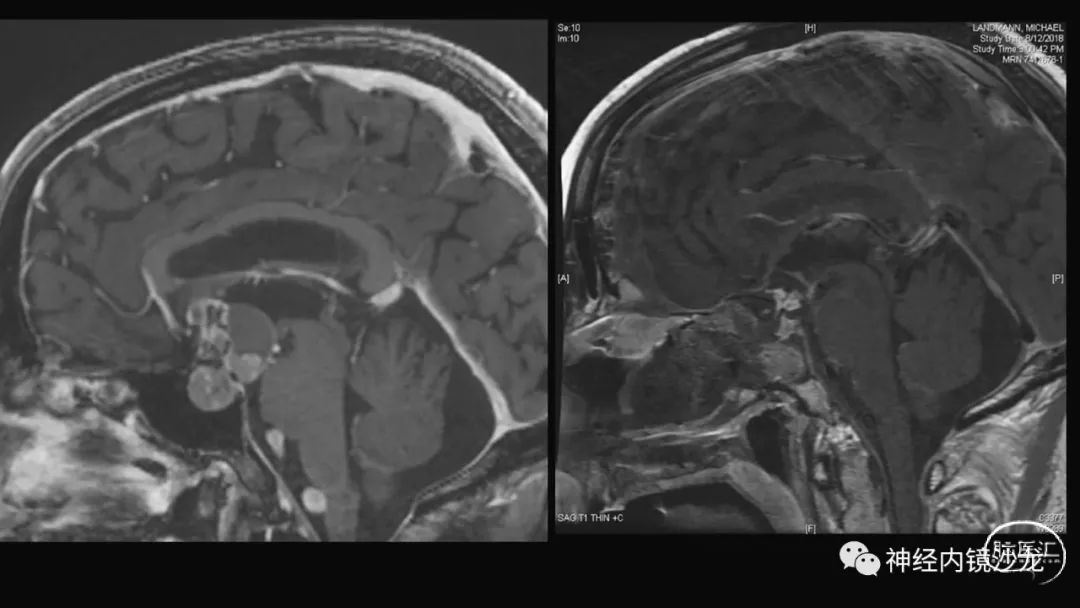

从事神经外科十余年,擅长神经外科肿瘤诊治,尤其是神经内镜微创手术治疗垂体瘤、颅咽管瘤、脑膜瘤等颅底肿瘤